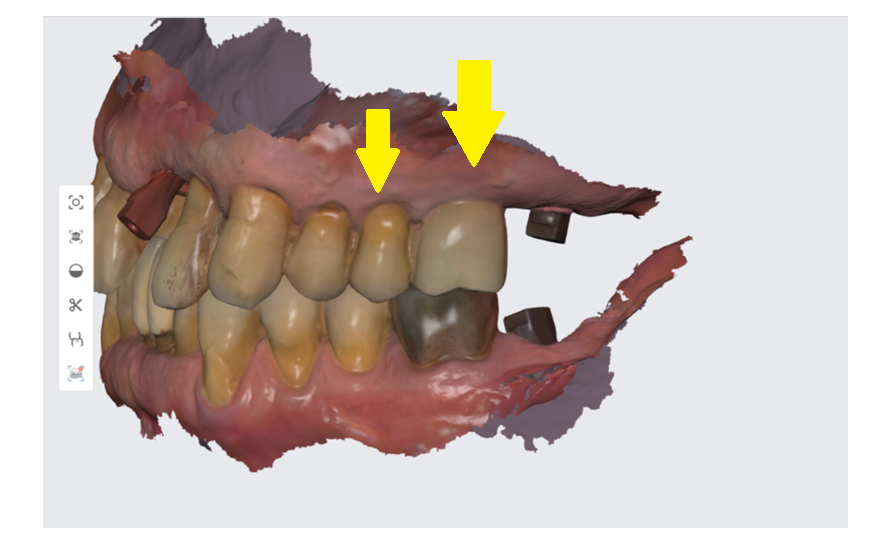

어금니 크기 차이가 많이 나죠~? 실제 이름도 작은 어금니와 큰 어금니입니다 .

231125